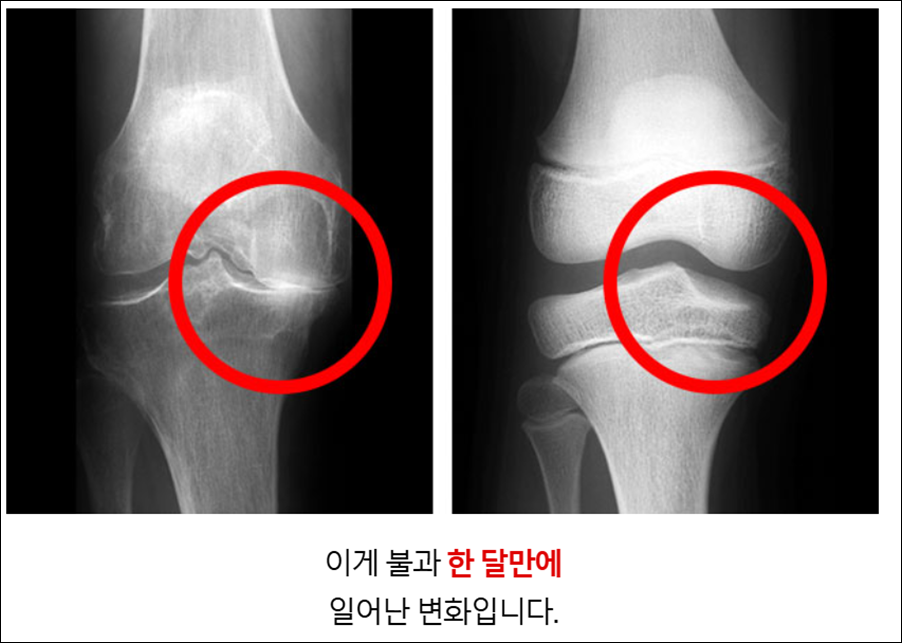

2) 연골 보호 및 재생 촉진으로 관절 기능 향상

연골은 관절의 충격을 흡수하고 부드러운 움직임을 가능하게 하는 중요한 조직입니다. 퇴행성 관절염은 이 연골이 닳아 없어지면서 발생하죠.

마가목은 연골을 구성하는 성분인 콜라겐 합성을 촉진하고, 연골을 파괴하는 효소의 활성을 억제하여 연골 손상을 막아줍니다.

엉겅퀴의 실리마린 또한 항산화 작용을 통해 연골 세포를 보호하고 손상된 연골의 회복을 돕는 것으로 알려져 있습니다. 연골이 건강해지면 관절의 움직임이 부드러워지고, 통증 역시 자연스럽게 줄어들게 됩니다.